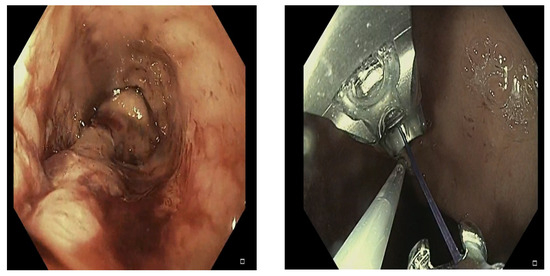

2.3. Procedure